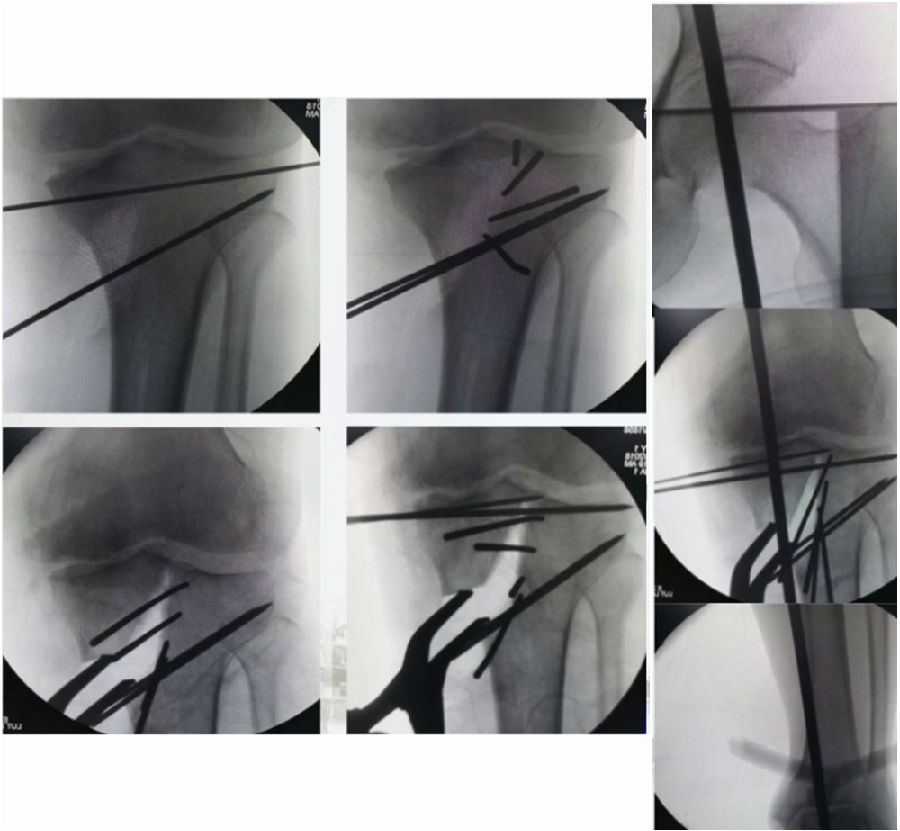

术中影像

结合影像学来看,该患者单纯用闭合截骨或开放截骨,对肢体均有影响,所以决定采用混合型截骨。术中混合截骨旋转中心选在内外1/3处,先做闭合楔,然后顺势将开放楔敲开,达到术前设计的目标力线。术后随访力线达到要求。

术中先打克氏针确定截骨方向,先做关节内截骨,截完后测量下肢力线,发现并没达到术前设计的Fujisawa点。

术中影像资料

随后用骨刀继续向前敲,做HTO内侧开放楔,截骨完成后内侧固定,并测量下肢力线,此时达到术前设计的要求。